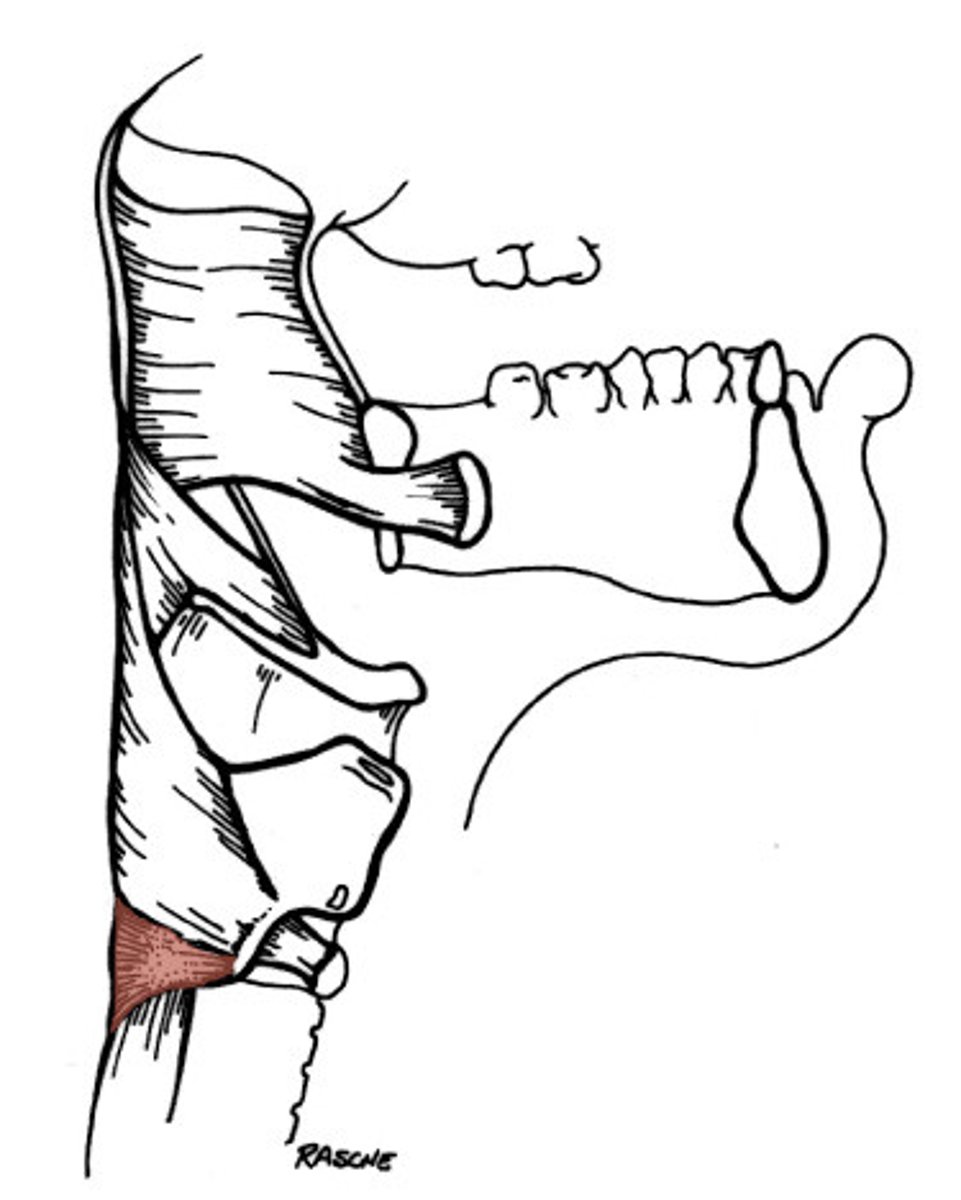

Inferior Constrictor -

Cricopharyngeus Description

Part of Inferior constrictor

Muscular component of upper esophageal

sphincter (UES)

Origin - cricoid cartilage

Course - fans out posteriorly and medially

Insertion - midline raphe

Action - open and close upper esophageal

sphincter

Inferior Constrictor -

Cricopharyngeus Figure